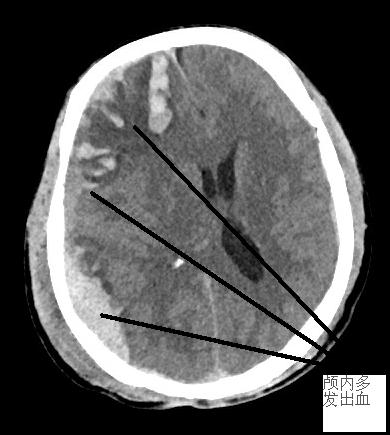

患者盧先生,男,52歲,上班時從約2米高的位置摔下,當(dāng)時呈嗜睡狀態(tài),工友趕緊送至我院急診科。經(jīng)CT檢查,提示多發(fā)外傷性腦出血,出血量中等。聯(lián)系家屬后,收住六病區(qū)神經(jīng)外科病床,先予以保守治療。第二天,患者意識障礙較前一天有所加重,呈昏睡狀態(tài),一側(cè)肢體活動減少,考慮病情惡化,隨即緊急復(fù)查CT,發(fā)現(xiàn)顱內(nèi)出血大量增加,顱內(nèi)壓力高,腦溝腦回、側(cè)腦室受壓,中線左偏,環(huán)池變窄,需緊急進(jìn)行手術(shù),告知家屬病情并取得手術(shù)知情同意后,在積極做術(shù)前準(zhǔn)備的同時,立即聯(lián)系福醫(yī)大附二院神經(jīng)外科當(dāng)班專家,準(zhǔn)備就緒后送入手術(shù)室。手術(shù)中,發(fā)現(xiàn)顱內(nèi)出血多發(fā)、量大,壓力高,腦組織受壓,立即予以充分清除血腫,腦組織壓力隨即減低,腦血管搏動有力。

手術(shù)前后對比